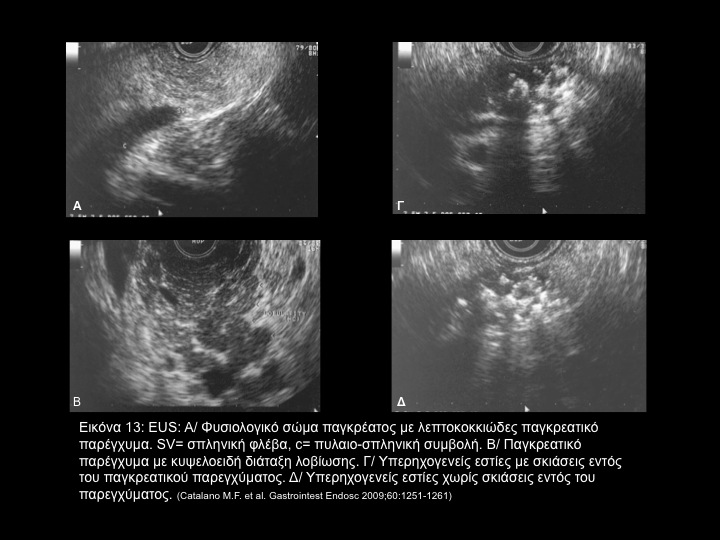

H έλευση της ενδοσκοπικής υπερηχογραφίας (ΕUS) ήταν σημαντική πρόοδος στην διαγνωστική προσέγγιση των ασθενών με διαταραχές του γαστρεντερικού και μη συστήματος. Βέβαια δεν έχει διευκρινισθεί πλήρως κατά πόσον ισχύει το ίδιο στην αξιολόγηση ασθενών με χρονία παγκρεατίτιδα, ιδιαίτερα στις περιπτώσεις εκείνες με πρώϊμες ή ακαθόριστες μορφές χρονίας παγκρεατίτιδος. Περαιτέρω, μελέτες χρειάζονται για να καθορισθούν τα χαρακτηριστικά, η σχετική προγνωστική αξία κάθε χαρακτηριστικού και κυρίως η εδραίωση ενός ιδεώδους αριθμού κριτηρίων που θα συμβάλλουν στην προγνωστική αξιολόγηση κάθε περιπτώσεως.

Επί του παρόντος, μετά από συνδιάσκεψη ειδικών εμπειρογνωμόνων και με συναινετική διαδικασία έχουν όρισθεί τα κριτήρια ‘Rosemont’, προκειμένου να υπάρξει επικοινωνία στον καθορισμό της σοβαρότητος της παθολογικής αυτής καταστάσεως. (Πίνακας 1, Πίνακας 2, Εικόνα 13, Εικόνα 14, Εικόνα 15)

6. Catalano M.F., Sahai A., Levy M., Romagnuolo J., et al. EUS-based criteria for the diagnosis of chronic pancreatitis: the Rosemont classification. Gastrointest Endosc.  2009;60(7):1251-1261.